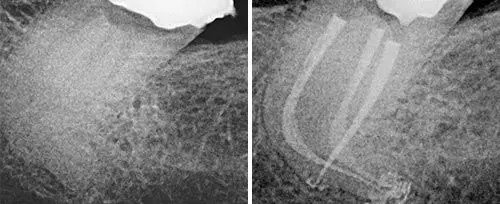

Endodontic Treatment